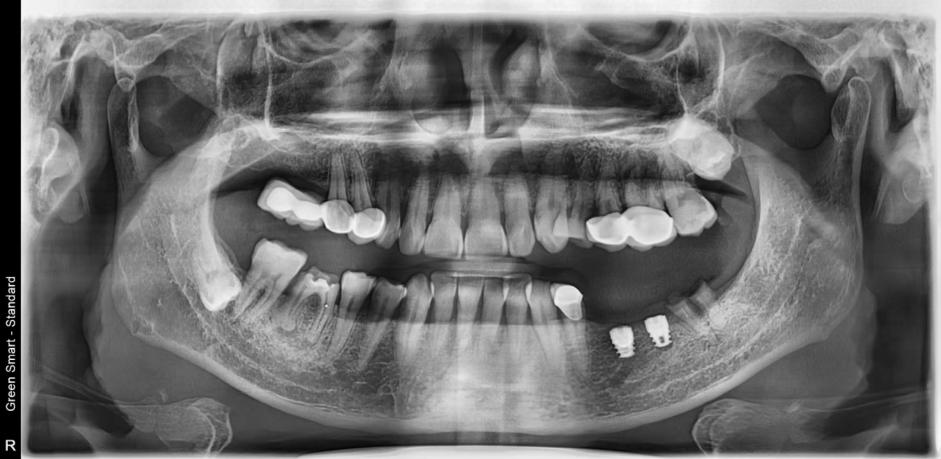

植牙後:(手術種植牙術後第一期照片)

擅長微創種植、數字化單顆種植牙,案例三:

種植牙前: